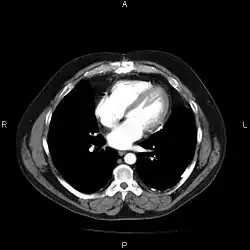

A picture archiving and communication system (PACS) is a medical imaging technology which provides economical storage and convenient access to images from multiple modalities (source machine types).[1] Electronic images and reports are transmitted digitally via PACS; this eliminates the need to manually file, retrieve, or transport film jackets, the folders used to store and protect X-ray film. The universal format for PACS image storage and transfer is DICOM (Digital Imaging and Communications in Medicine). Non-image data, such as scanned documents, may be incorporated using consumer industry standard formats like PDF (Portable Document Format), once encapsulated in DICOM. A PACS consists of four major components: The imaging modalities such as X-ray plain film (PF), computed tomography (CT) and magnetic resonance imaging (MRI), a secured network for the transmission of patient information, workstations for interpreting and reviewing images, and archives for the storage and retrieval of images and reports. Combined with available and emerging web technology, PACS has the ability to deliver timely and efficient access to images, interpretations, and related data. PACS reduces the physical and time barriers associated with traditional film-based image retrieval, distribution, and display.

Most PACS handle images from various medical imaging instruments, including ultrasound (US), magnetic resonance (MR), Nuclear Medicine imaging, positron emission tomography (PET), computed tomography (CT), endoscopy (ES), mammograms (MG), digital radiography (DR), phosphor plate radiography, Visible Light Photography (VL), Histopathology, ophthalmology, etc. Additional types of image formats are always being added. Clinical areas beyond radiology; cardiology, oncology, gastroenterology, and even the laboratory are creating medical images that can be incorporated into PACS. (see DICOM Application areas).